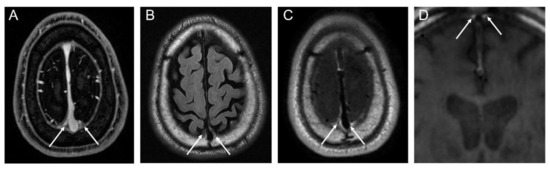

2.4. Segmentation of Dura-Associated Lymphatics